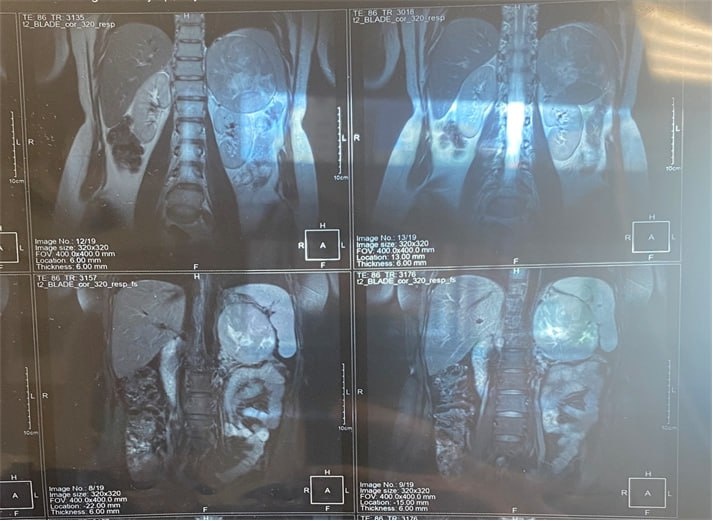

Результаты МРТ указали на крупное образование размером 94×97×140 мм, оттесняющее левую почку.